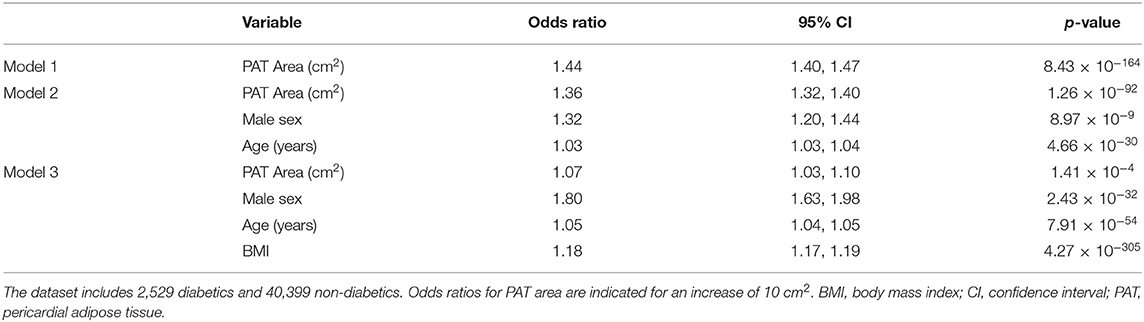

Association With Diabetes

Given the established association between diabetes and increased PAT, we tested the clinical validity of our PAT measures through consideration of associations with this condition. We applied our automated CMR PAT analysis tool to the entire UKB Imaging cohort for whom adequate imaging was available (n = 42,928). Diabetes was coded based on self-report of the diagnosis, self-reported use of “medication for diabetes,” or serum glycosylated hemoglobin >48 mmol/mol. We tested the association of PAT area with diabetes status in multivariable logistic regression models with adjustment for age, sex, and body mass index (BMI). We present the results as odds ratio associated with a 10 cm2 increase in PAT with corresponding 95% confidence intervals and p-values.

Application to the UK Biobank Imaging Cohort and Association With Diabetes

We applied our neural network to CMR scans from 45,519 UKB participants. We excluded cases with a segmentation Dice score of <0.6 (n = 2,591, 5.7%). The remaining 42,928 participants were included in the analysis; of these, 2,529 were diabetic. Consistent with existing evidence (2), larger PAT area was associated with greater risk of diabetes in univariate and multivariable models (Table 2). In fully adjusted models, every 10 cm2 increase in PAT was associated with ~7% greater likelihood of diabetes independent of age, sex, and BMI.